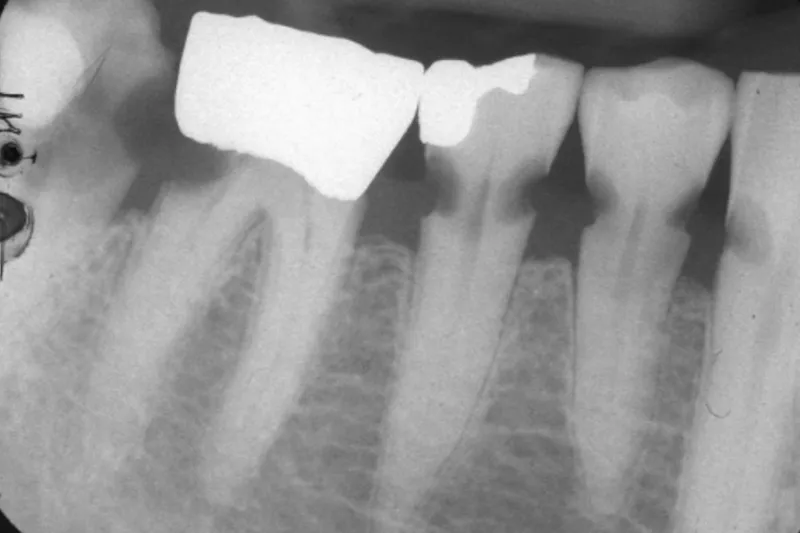

Så længe den almene og kognitive tilstand er god, opretholdes tandsundheden. Men med svigtende autonomi, polyfarmaci og nedsat spytfunktion kan den orale sundhed hurtigt forringes – i takt med at mulighederne for terapeutisk intervention forringes.

Tandtab er ikke aldersbetinget – men aldersrelateret. Ældre har en forøget risiko for at udvikle orale sundhedsproblemer. Det er væsentligt at identificere risikopatienter. Indsigt i, hvordan sygdomsrisiko varierer fra individ til individ, er grundlaget for et fleksibelt indkaldeinterval, som er baseret på den enkeltes behov (cariesaktivitet, almen sundhedstilstand, mundtørhed, evne til egenomsorg, komplicerede protetiske konstruktioner etc.). Oftest bliver udgifterne til reparation i form af menneskelige og økonomiske resurser betydeligt større end ved de forebyggende tiltag, som rutinerne beskriver. Konsekvenserne af manglende vedligeholdelse er velkendte: tab af tænder, dårligere oral og generel sundhedstilstand, social stigmatisering, ernæringsproblemer, smerter etc. Forebyggelse er bedst – og billigst.